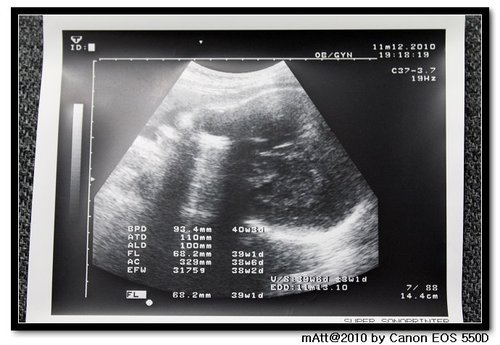

2010/11/12

今天再去產檢

三天後就是預產期了!

所以醫生建議過預產期就可以催玩子出來了...

今天3175g...逼近醫生建議的2800-3200的最佳出生體重...